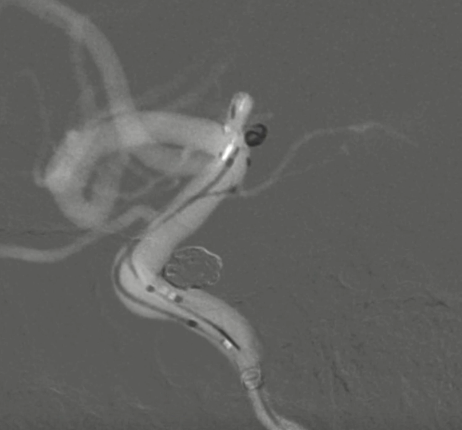

术后正侧位造影:Raymond Ⅲ级

术后支架重建:支架打开良好,近端Marker位于颈内动脉分叉处

术后Vaso CT未见出血,患者神清语利,神经系统查体阴性。

继续填入Target 1.5/2弹簧圈成篮,后完全释放支架,其近端位于颈内动脉分叉处,远端位于A1远端。